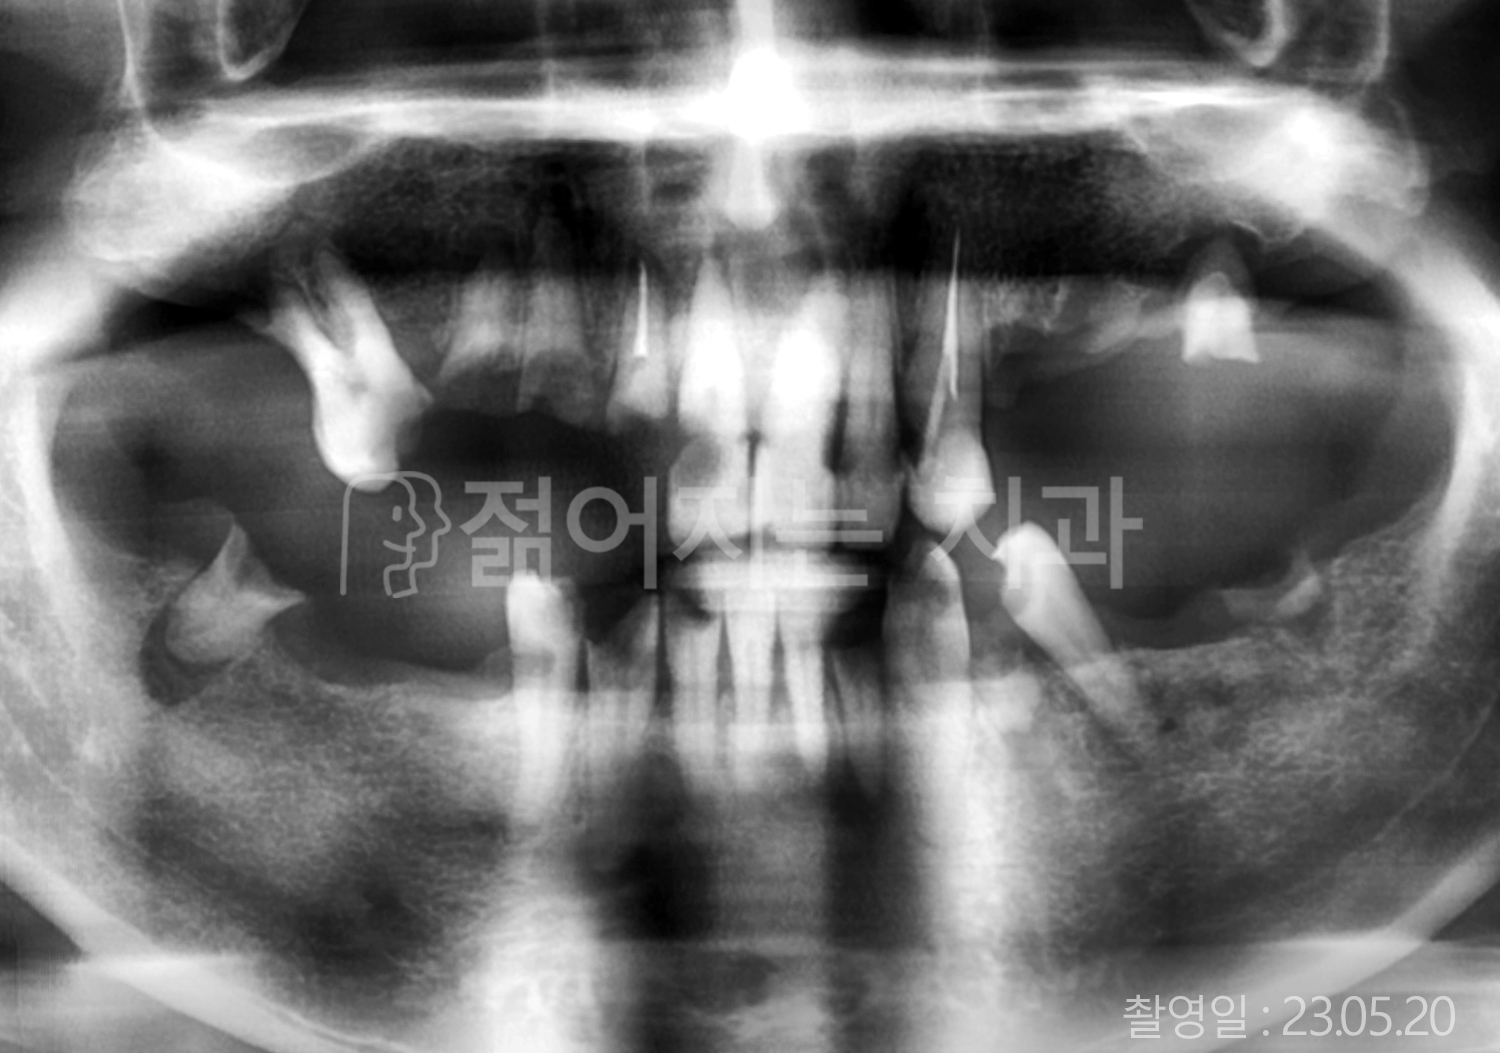

• 70대 고혈압, 고지혈증 전체치아 10개 이상 임플란트

• 60대 당뇨, 간염 전체치아 10개 이상 임플란트

• 80대 골다골증 전체치아 6개 이상 임플란트

• 70대 고혈압, 당뇨 전체치아 10개 이상 임플란트

• 60대 간 질환 전체치아 10개 이상 임플란트

• 60대 전체치아 10개 이상 임플란트

• 70대 전체치아 10개 이상 임플란트

• 50대 전체치아 10개 이상 임플란트

• 60대 고혈압, 고지혈증 전체치아 10개 이상 임플란트

• 40대 고지혈증, 뇌혈관 질환 전체치아 10개 이상 임플란트